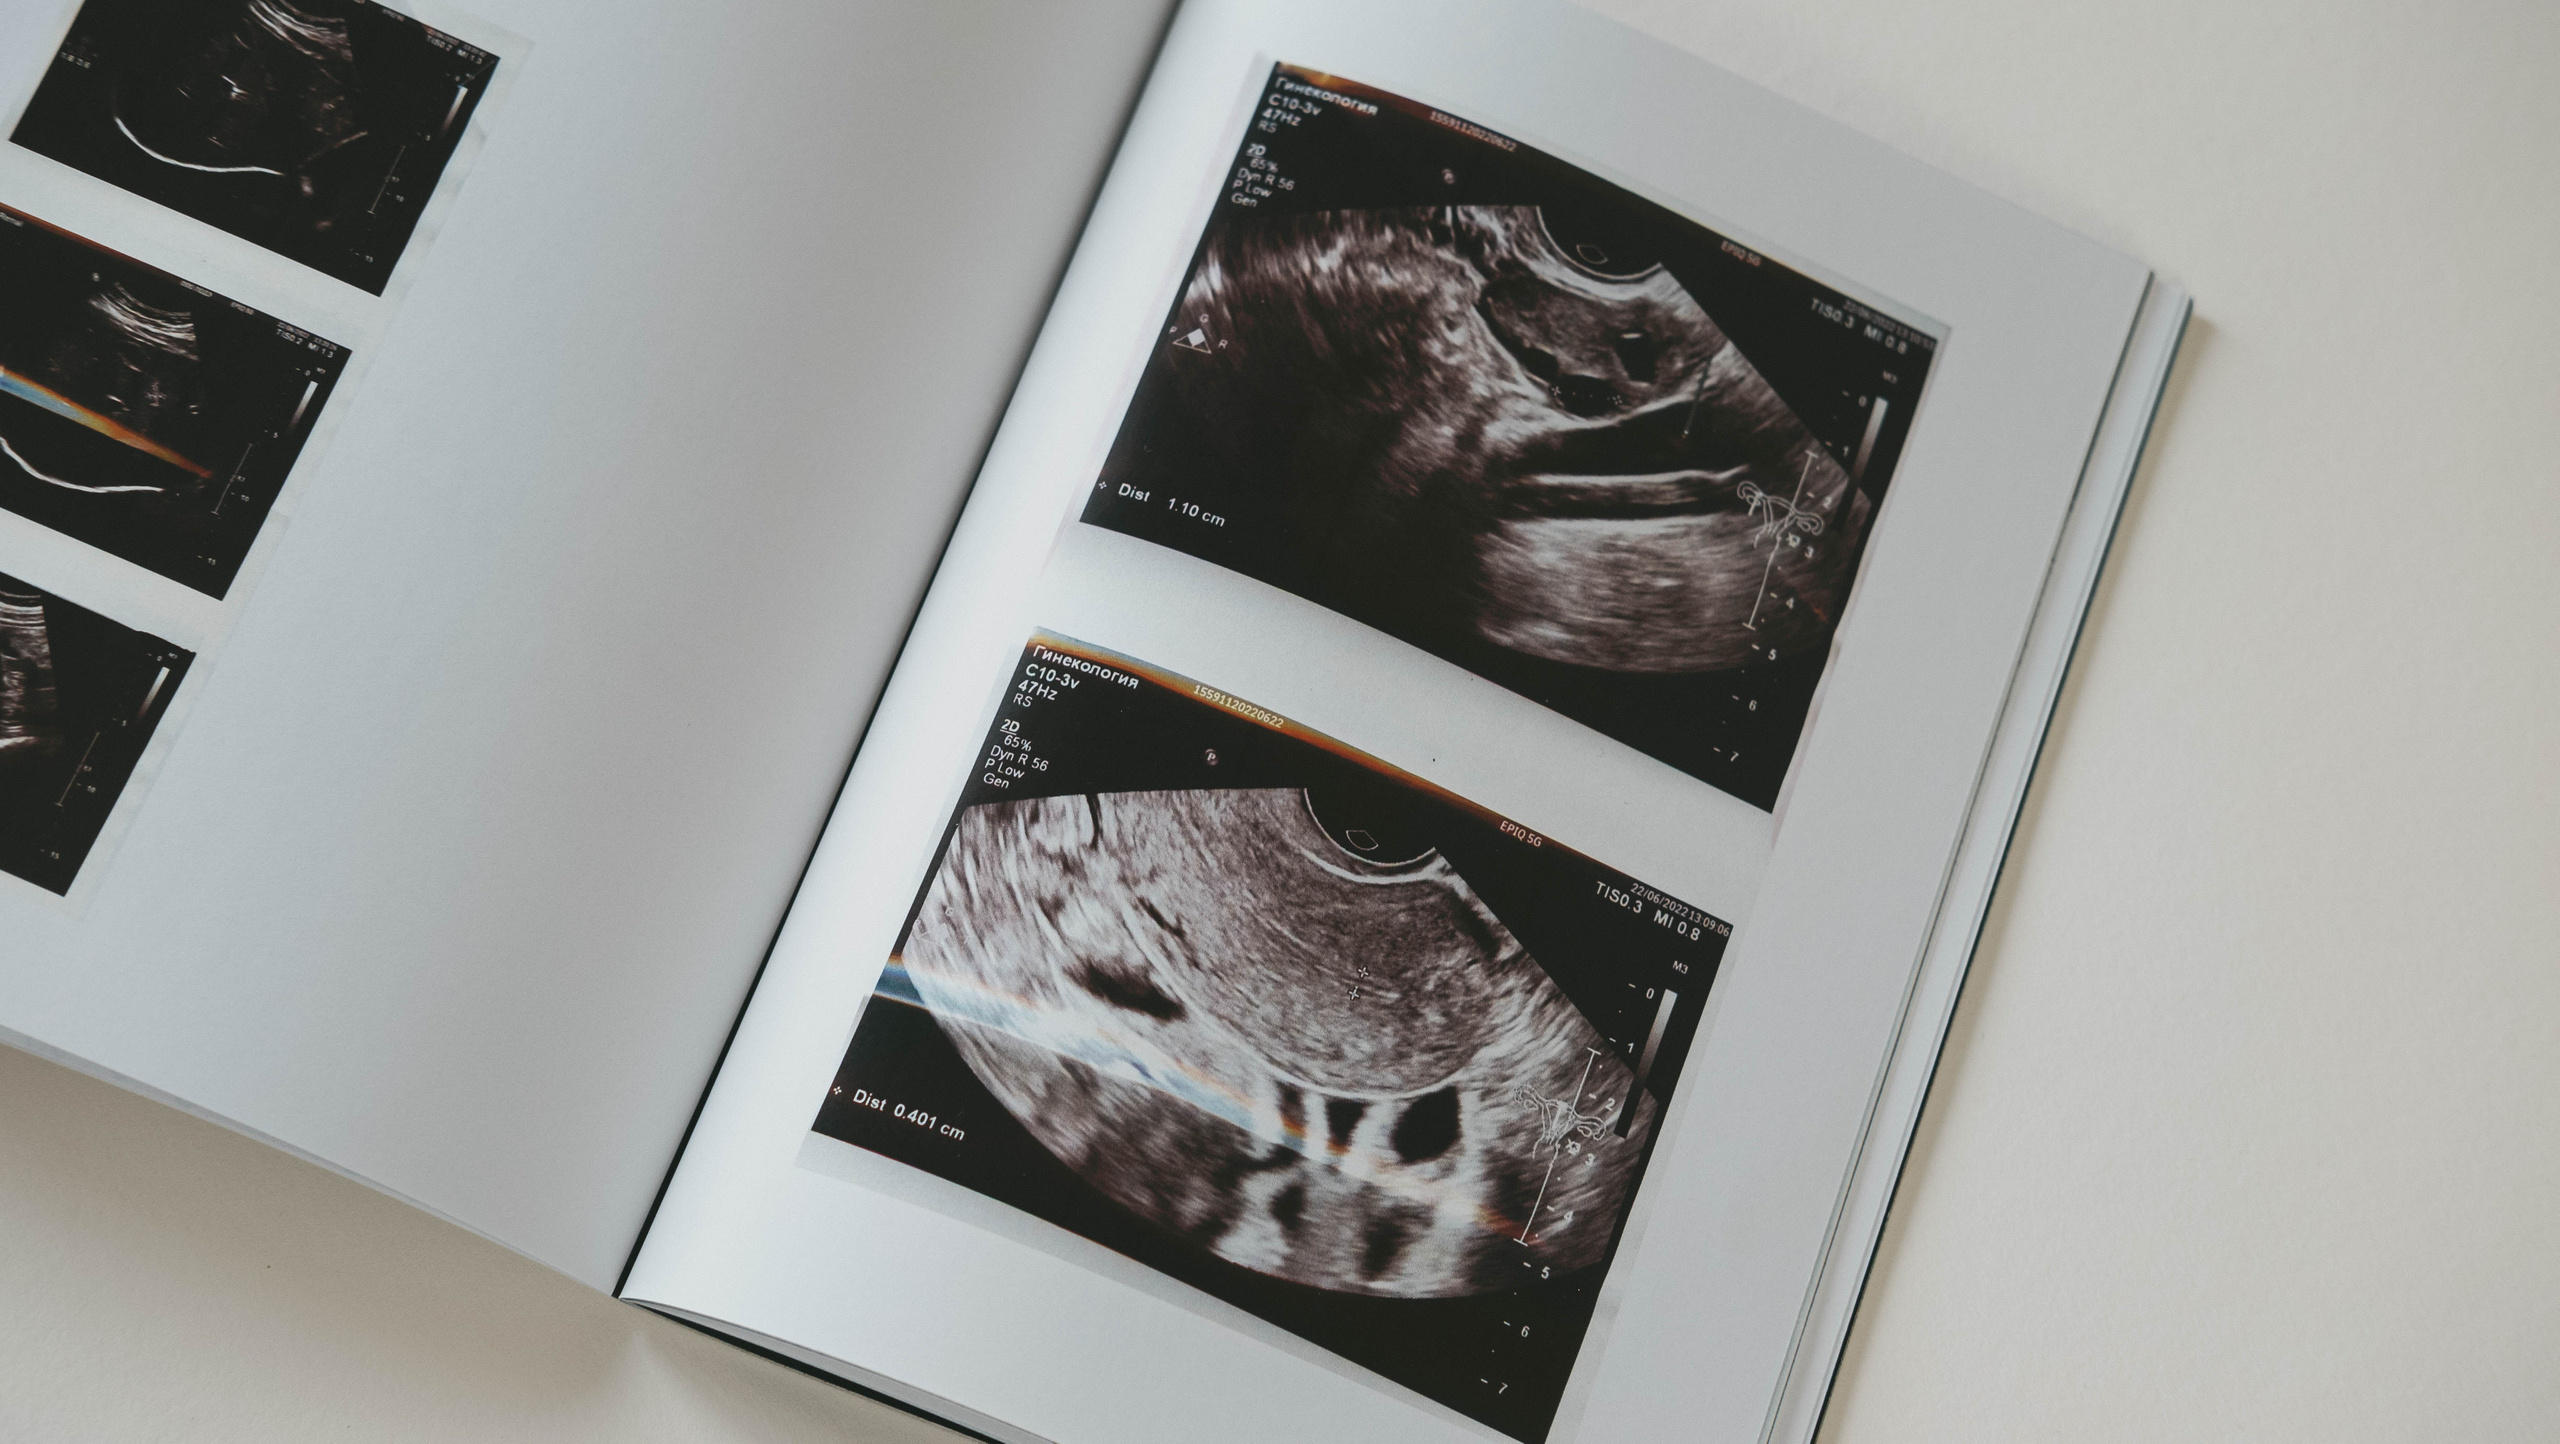

В 2021 году я узнала, что мне необходимо сделать операцию, чтобы удалить полип. Из-за коронавируса операция перенеслась. Во время операции берут материал, а затем его отправляют на гистологию и около месяца необходимо ждать результат.